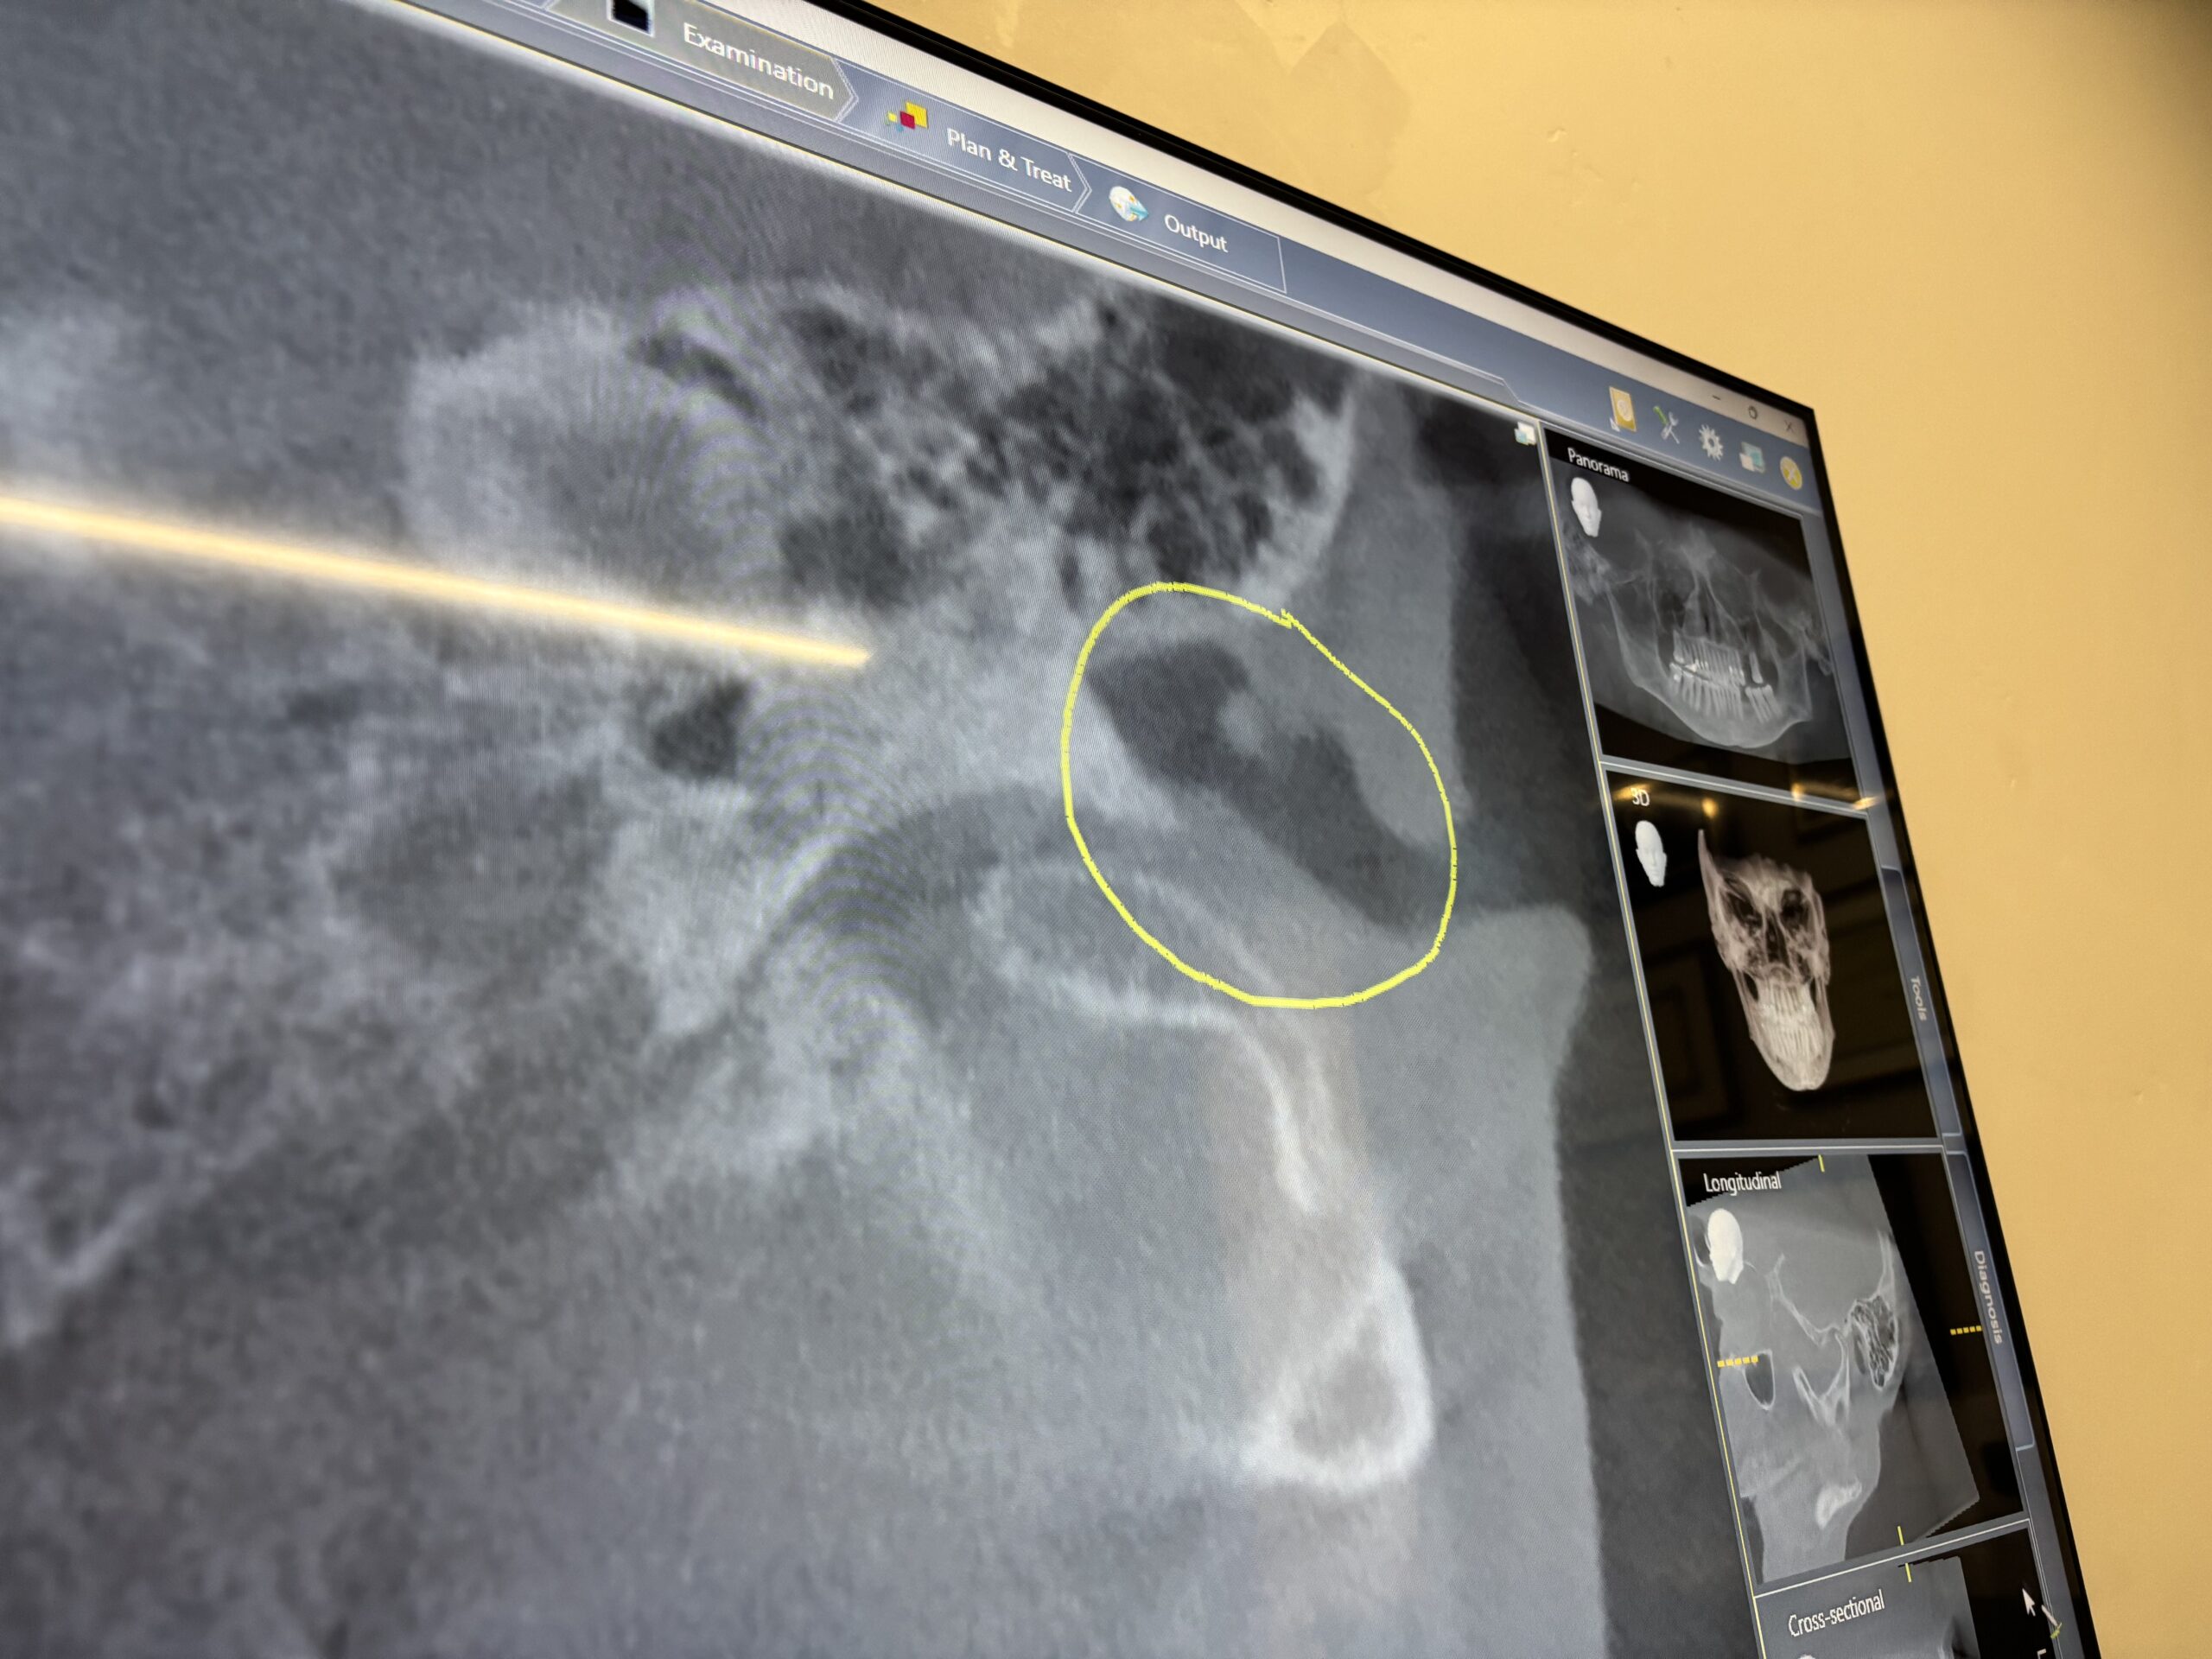

Ten days later I’m sitting with my Phoenix dentist relating my Raphe story as he pulls up my recent April scan.  Unfortunately, a CBCT scan is not the appropriate scan to study Raphe. For whatever reason, I asked him to look in the Eustachian tube area based on back-and-forth conversations with my Santa Cruz osteopath about this area as a potential source of my symptoms. This unplanned conversation produced a large surprise.

Zooming into this area, the dentist exclaimed,

Look at this!”.

The big-screen TV displaying the CBCT scan is

definitely ‘in-your-face’. It was very easy to see what the dentist was referring to in my Eustachian tube as he manipulated the scan forwards and backwards.

I took my laptop to my ENT appointment to show the CBCT scan.  That was quite an experience in technology.

I finally met with success connecting into their network with the help of a nurse

and was able to access the scan on the cloud.

My ENT took one look, moved around the axial view a bit and stated while he proceeded to look in my ear:

“That’s not your Eustachian tube…that’s your ear canal.

And most likely a piece of ear wax was present at the time of the scan.”

Well, so much for a dentist reading a scan of the ear!

I’m certainly glad that I am having this reviewed by a radiologist.

And I will be most curious to see what my San Jose dentist says about this “thing”.